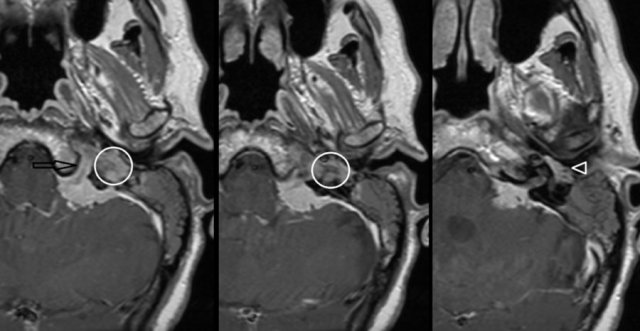

Hypervascular metastases or meningioma

Highly vascularized bone lesions, like osseous hemangioma, basal meningioma, Langerhans cell histiocytosis, or bone metastases, have been described as possible causes of pulsatile tinnitus.

On the left a meningioma on MRI.

Axial contrast-enhanced T1-W images.

Enhancing mass located in the left cerebellar-pontine angle with extension into hypoglossal canal (arrow), jugular plate (encircled), and the middle ear (arrowhead).